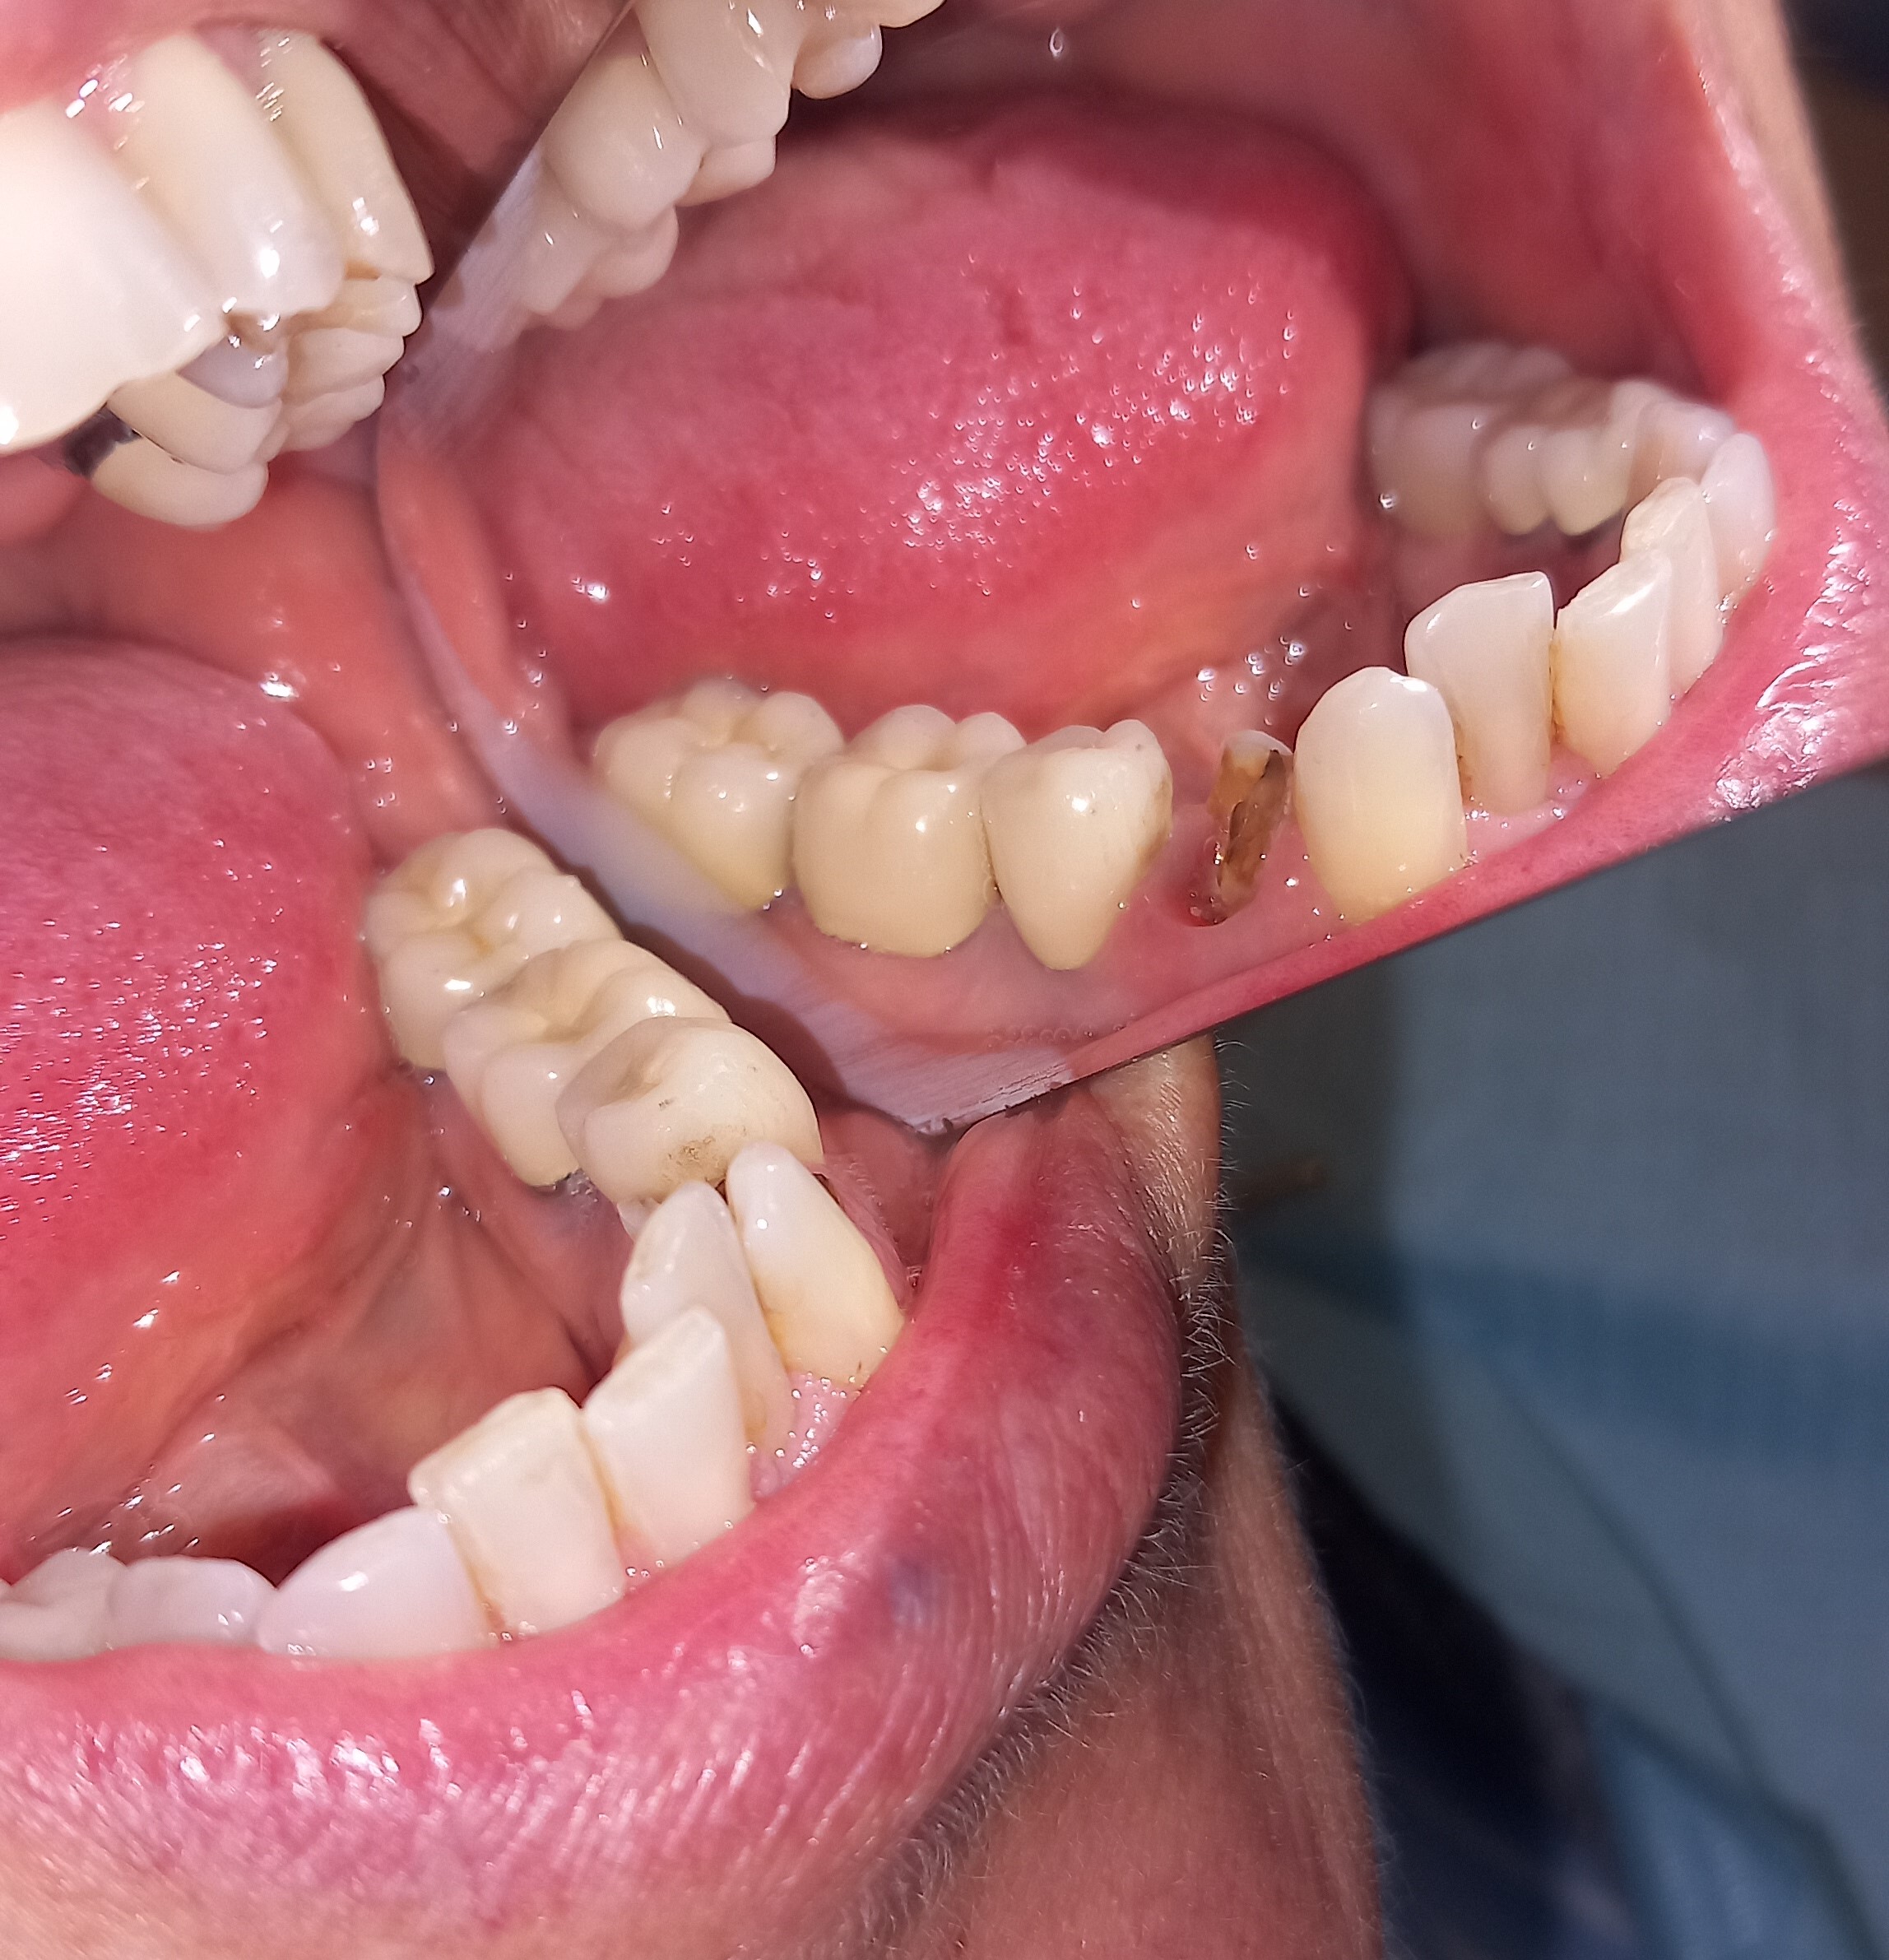

Ο ασθενής δεν είναι ευχαριστημένος με την αισθητική των 6 άνω πρόσθιων δοντιών. Επιπρόσθετα αυτά τα δόντια είχαν παλιές μεγάλες ανασυστάσεις, οι οποίες είχαν επανατερηδονιστεί. Για όλους τους ανωτέρους λόγους αποφασίστηκε, μετά από την απαραίτητη συζήτηση με τον ασθενή η αποκατάσταση των δοντιών με ολοκεραμικές θήκες. Τα δόντια τροχίστηκαν, αντικαταστάθηκαν οι παλιές εμφράξεις των δοντιών και στη συνέχεια λήφθηκαν αποτυπώματα, τα οποία στάλθηκαν στον οδοντοτεχνίτη. Σε όλη τη διάρκεια, που ο οδοντοτεχνίτης κατασκεύαζε τις νέες προσθετικές αποκαταστάσεις ο ασθενής φορούσε προσωρινές θήκες, οι οποίες είχαν ικανοποιητική αισθητική εμφάνιση.

Είναι σημαντικό να τονιστεί οτι ο ασθενής επιθυμούσε οι θήκες των 6 άνω πρόσθιων δοντιών να είναι αισθητά λευκές, παρόλο που διέφεραν χρωματικά από τα υπόλοιπα δόντια.

Ο ασθενής είναι ευχαριστημένος τόσο με την αισθητική όσο και με τη λειτουργία των νέων προσθετικών αποκαταστάσεων.

Αρχική κλινική εικόνα των 6 άνω πρόσθιων δοντιών

Προσωρινή αποκατάσταση των 6 άνω πρόσθιων δοντιών

Τελική κλινική εικόνα των 6 άνω πρόσθιων δοντιών